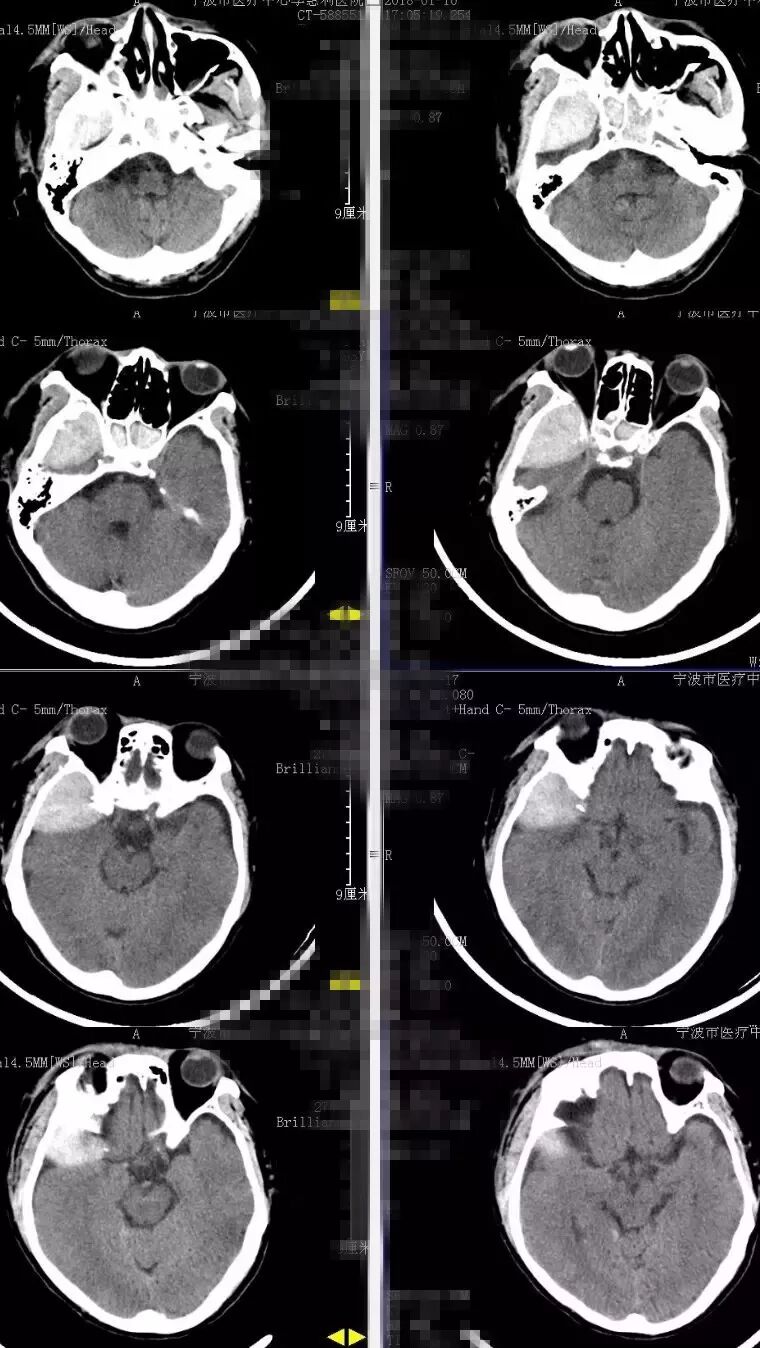

2018-2-13 CTA提示右颞部DAVF可能(图6),建议DSA。仔细阅片CTA未见明显引流静脉,考虑右侧脑膜中动脉假性动脉瘤可能更大。次日行 DSA检查,证实为“右侧脑膜中动脉假性动脉瘤”(图7)。当日即行“右侧翼点入路,脑膜中动脉假性动脉瘤切除加血肿清除术”(图8)。病理回报:镜下纤维细胞增生,可见血凝块伴机化(图9)。2018-2-27 复查CTA提示右侧脑膜中动脉假性动脉瘤术后改变,未见残余及复发(图10)。

图6. 2018-2-13 CTA提示右颞部DAVF可能。

图10. 2018-2-27 复查CTA提示右侧脑膜中动脉假性动脉瘤术后改变,未见残余及复发。